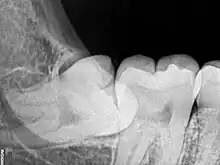

Risk factors of inferior alveolar nerve damage

Temporary and permanent inferior alveolar nerve (IAN) damage is a known complication of the surgical removal of impacted lower third molars, happening in 1 in 85 patients and 1 in 300 extractions, respectively. Studies have shown that certain risk factors may increase the likelihood of IAN damage. Proximity of the impacted third molar root to the mandibular canal, which can be seen in radiographs, has been shown to be a high-risk factor for IAN damage. Alongside this, the depth of impaction of the tooth, surgical technique and surgeons experience are all contributing risk factors for IAN damage during this procedure. Careful case-by-case consideration is crucial to avoid this risk.[43]